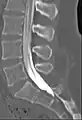

Myelogram showing arachnoiditis in the lumbar spine.

CT myelography

Contrast media is injected into the thecal sac. The subject is then rotated longitudinally a few times to ensure even coating of the contrast around spinal cord and reduce the possibility of layering of the contrast media just before CT scan.[1]